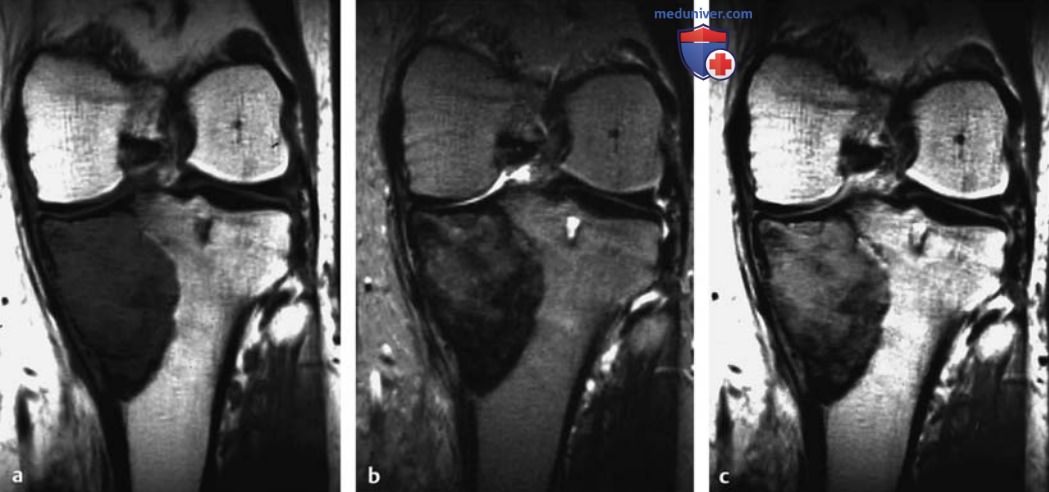

МРТ доброкачественных опухолей костей и опухолеподобных поражений

Рисунок 9. a-c Гигантоклеточная опухоль проксимального суставного конца большеберцовой кости.

а Т1в-SЕ-изображение во фронтальной плоскости.

b Т2в-ТSЕ-изображение во фронтальной плоскости.

c Т1 B-SE-изображение после контрастирования.

Визуализирована опухоль проксимального конца большеберцовой кости с гетерогенной интенсивностью сигнала при всех ИП. Поражение распространяется до субхондральной костной пластинки, пенетрирует кортикальный слой по медиальной поверхности и имеет небольшой экстраоссальный компонент. Распространенные отложения гемосидерина объясняют очень низкую интенсивность Т2в-сигнала от опухолевой ткани.